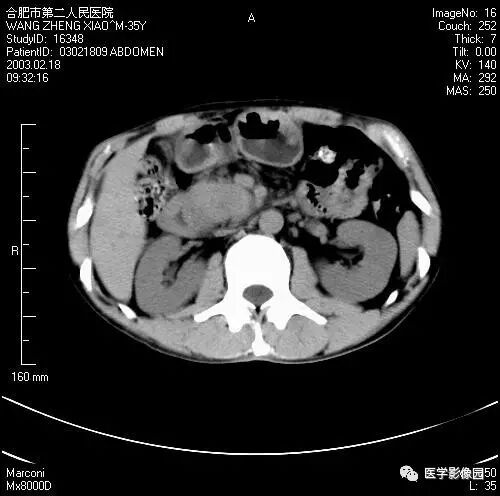

图6-4-13胰腺癌

CT平扫见胰体、尾部局限性肿大,

其内境界不清的低密度灶(↑);

肝右叶有多个低密度转移灶(长↑),

并见腹水